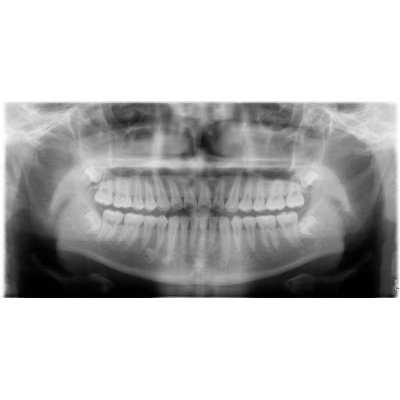

兒童牙科

乳齒:嬰兒出生後第六個月左右第一次長出來的牙會長滿20顆。

在周歲前開始定期牙科檢查

預防重於治療。通常在幼兒時期最常見的疾病-齲齒」。愈早作牙齒檢查,便有愈多的機會提早預防牙齒的發生。看牙不一定會痛!在沒有任何的病痛查,對幼兒來說,是一次的愉快經驗。

人工植牙

商品大圖